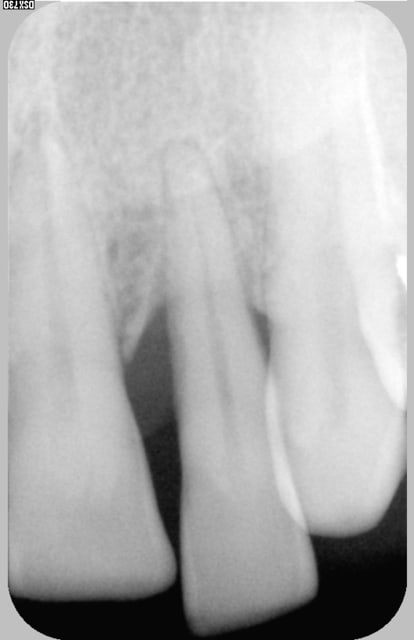

Je vais poster les 2 radios 2006 2007et une photo 2007 pas terrible car je ne suis pas équipée pour ça.

La 12 n'est plus mobile, mais toujours egréssée et vestibulée ,la gencive est encore un peu inflammatoire,(cf la photo) mais la radio montre que l'os alveolaire a bien réagi et il n'y a pas de poche.

Marcho radio sept 07 mtf60m - Eugenol